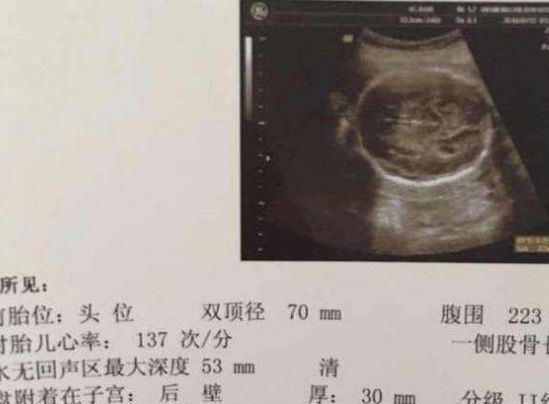

一般情况下,在产检单上,如果出现宝宝的胎心率的时候,也可以通过胎心率来判断自己腹中的宝宝到底是一个男孩子还是一个女孩子。正常情况下,如果胎心率一分钟能跳120到140之间的话,那么是比较正常的。而如果肚子里怀的是一个小王子的话,那么胎心率很有可能是在120到140之间每分钟。但是如果我们的准妈妈怀的是一个小公主的话,那么胎心率很有可能就会在150到160之间了。当然,如果宝宝的胎心率出现一些问题的时候,我们的医生也,会尽快的告诉我们的准妈妈的。

文章插图